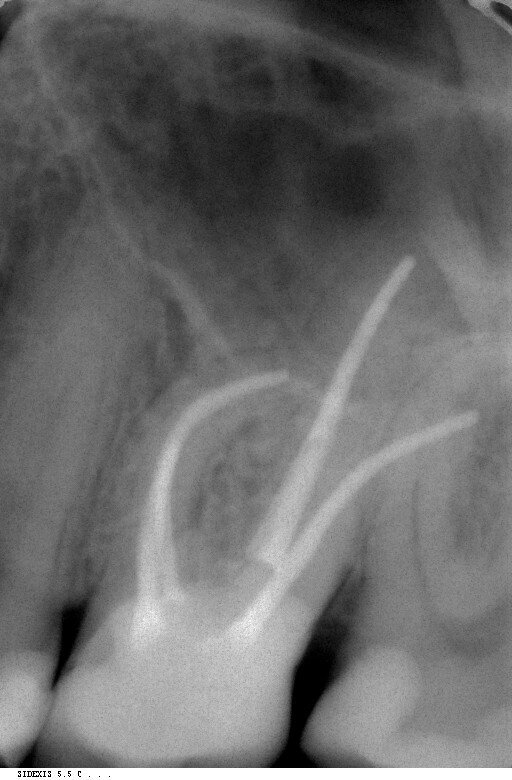

Fig.1: Inital situation.

A 36-year-old patient presented with acute pain in tooth #26 to our practice in October 2012. Radiographic diagnostics showed a deep carious defect distally (Fig. 1). On the basis of these clear findings, we recommended a root canal therapy. The patient agreed to the treatment. After application of the rubber dam, the affected tooth was first built up with composite for greater stability, and then a diamond drill was used to create the appropriate access. The pulp chamber was then opened. All crown pulp tissue was removed from the infected tooth in the process. Canal clearance was checked with a 10/.05 glide path file.